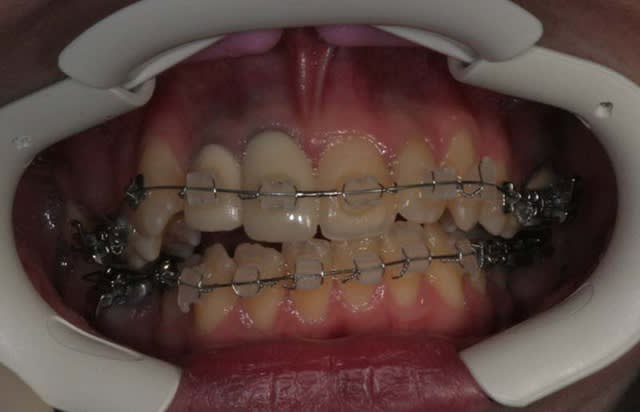

Suite :

J’ai pensé qu’il suffisait de déposer le Q.H. pour que les mouvements parasites s’arrêtent d’eux m

il n’en est rien : photo un mois après

malgré tout, les formes d’arcades s’arrangent !

a suivre Bjc.

6 tcnvtt - Eugenol

7 aokywu - Eugenol

1 p3qrc4 - Eugenol

Bjc.

14/03/2010 à 14h36

j'avais fabriqué une Cl. II.

là, j'ai eu un moment de découragement

@+ Bjc.

Je suis face à plusieurs Pbs.

continuer mon reformage tout en stoppant la version des Ant.

et la réduire, mais pour cela, il me faudra utiliser des élastiques de Cl. II. avec des arcs rigides et donc avoir fini le reformage

c’est la quadrature du cercle, il me faut choisir

je garde en priorité le reformage et pour bloquer (et essayer de commencer à réduire) la version des Ant. j’utilise un arc à mémoire de forme 16*x16* que je vais faire travailler avec du torque sur les Ant. en ligaturant en inter-actif et en post en passif, en ligaturant passif

l’effet d’expansion se surajoutera aux forces musculaires de l’orbiculaire pour stabiliser les Ant.

résultat: la situation s’améliore, j’ai pu inverser les tendances grâce à l’arc 16*x16* austénitique utilisé en parti en passif, et en parti en inter-actif, c. a. d. en gardant de la glisse tout en mettant du torque

(le 16*x16* est un arc magique que l’on ne peut malheureusement pas bien utiliser avec tous les systèmes à forces faibles)

OUF !!!